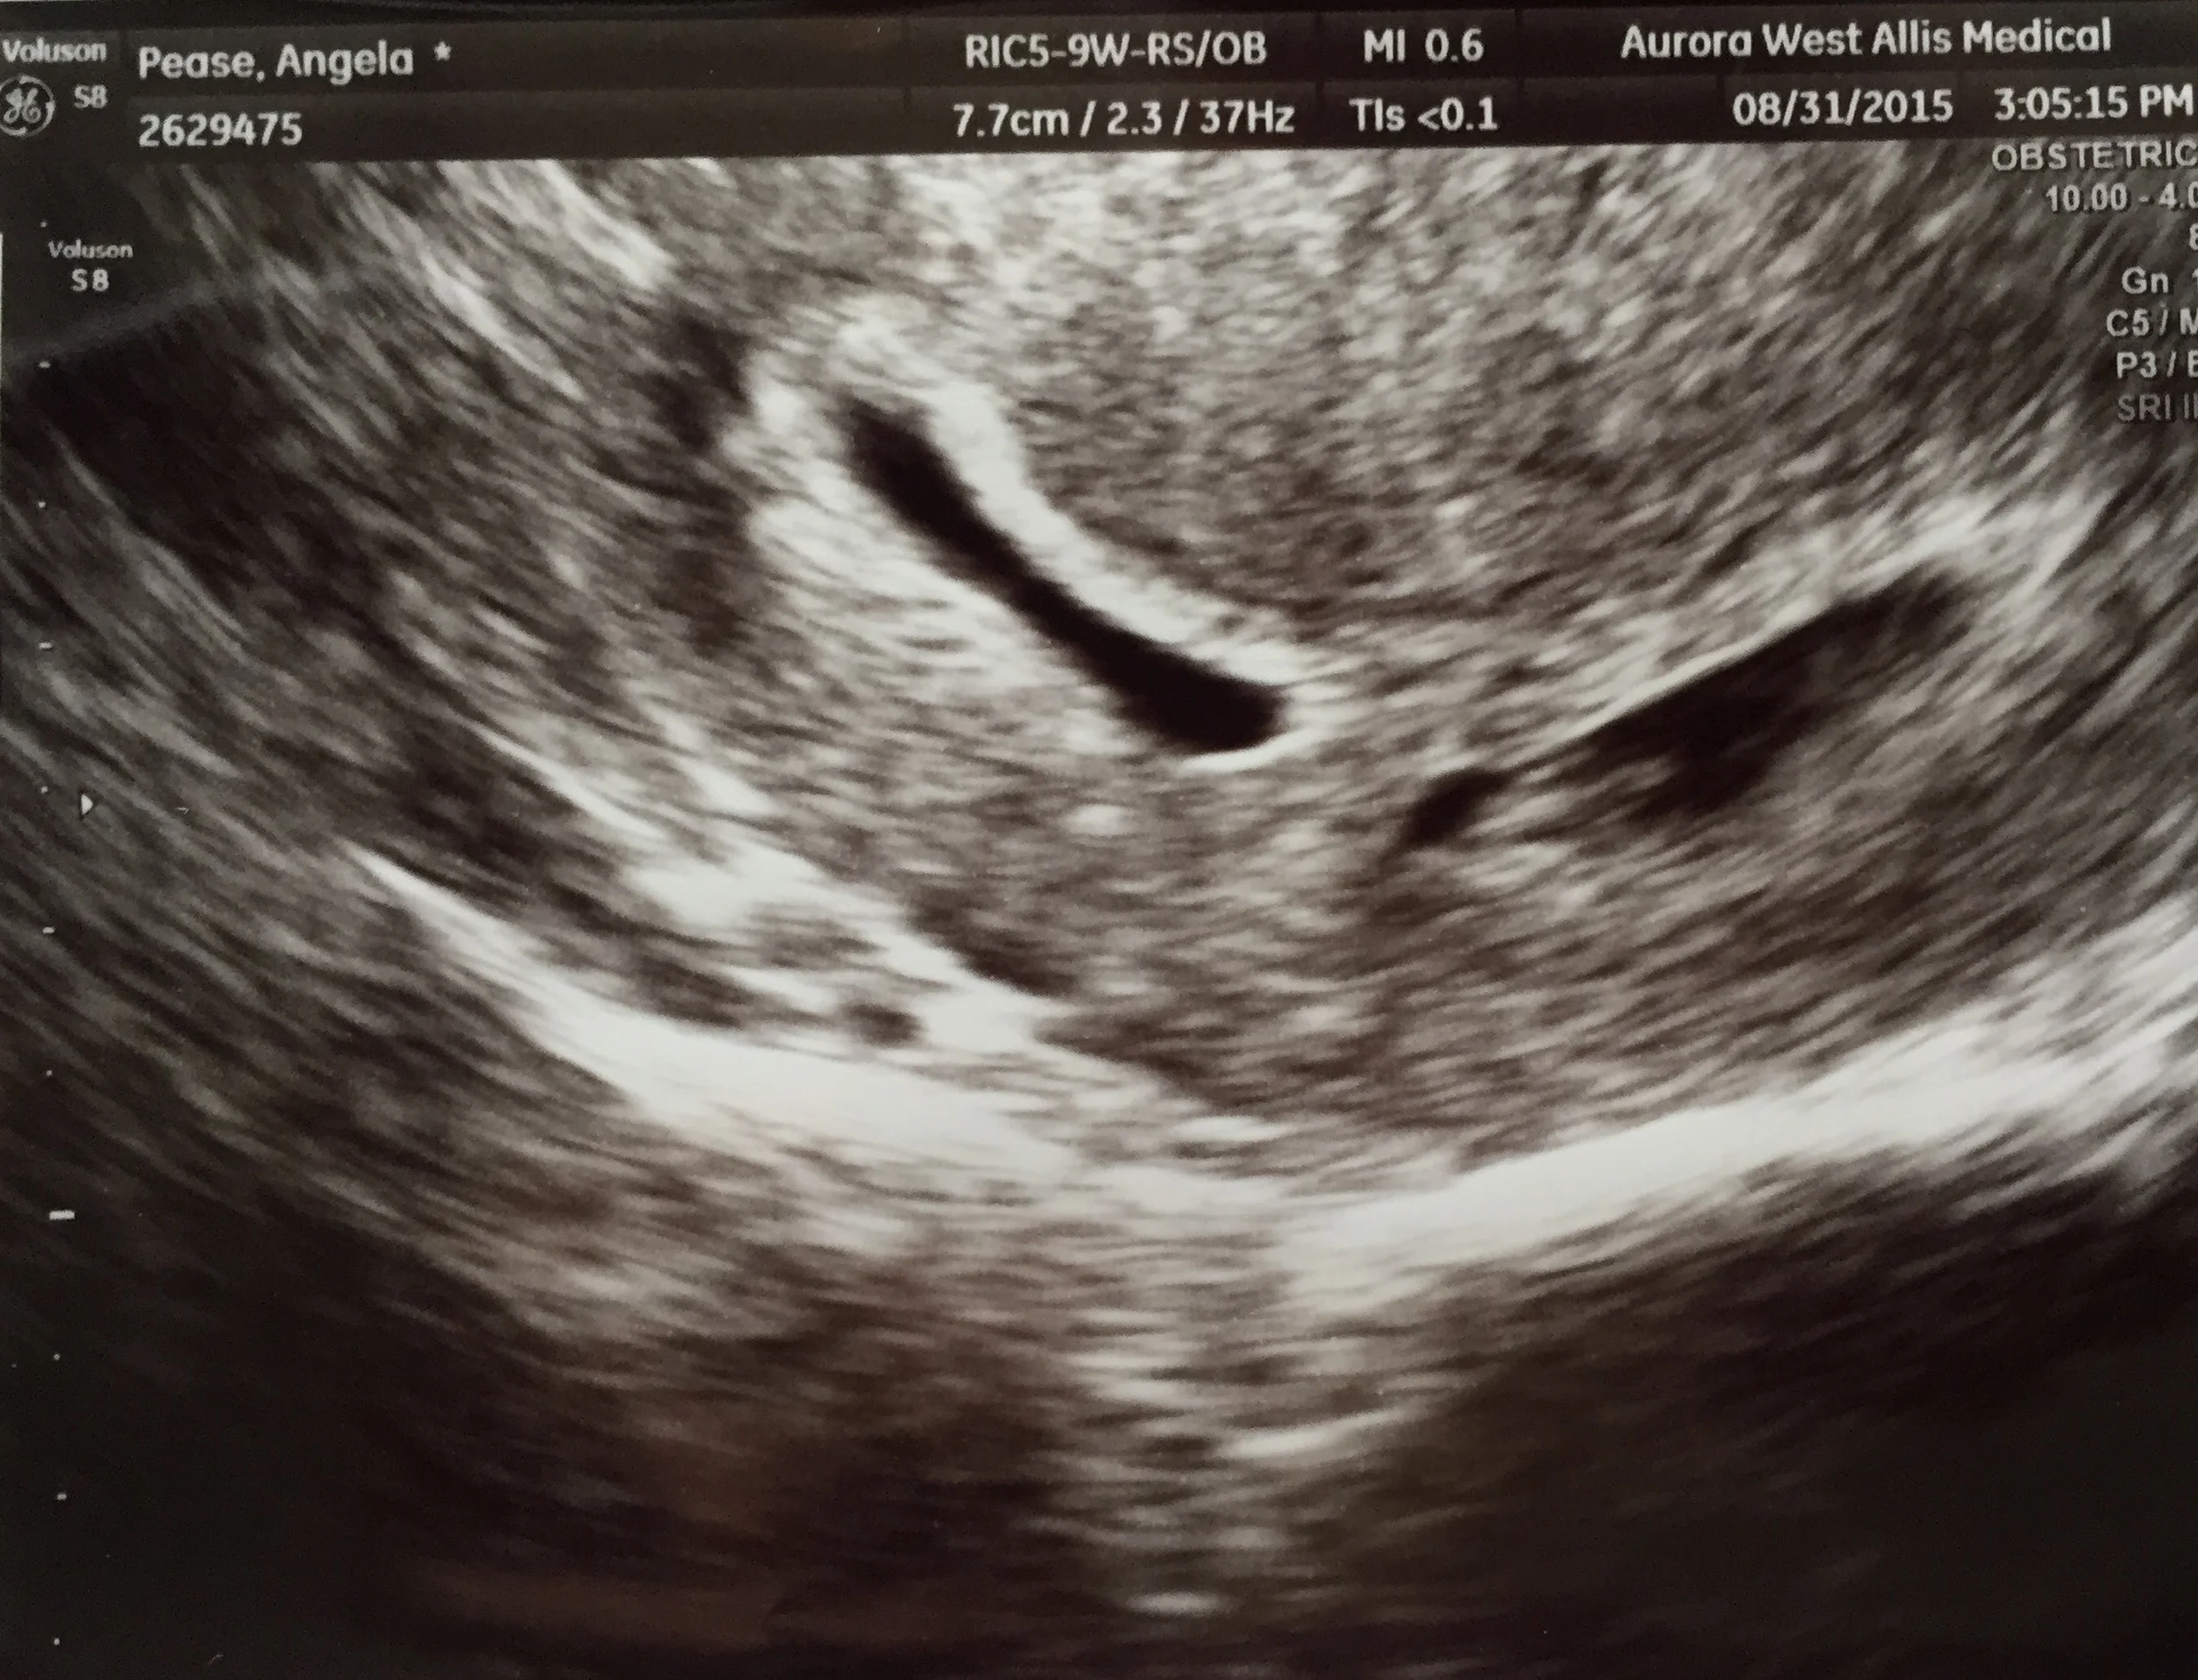

Ricky and I had our 6 1/2 week ultrasound this morning and we learned we are expecting twins! Both babies had a heartbeat that we could see on the ultrasound and measured well.

We have our next ultrasound in 2 weeks.